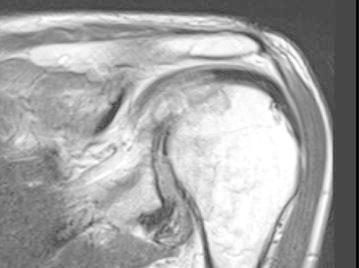

Radiographs of the hands showed erosions in the left third DIP and right second DIP, in addition to mild joint space narrowing with mild diffuse osteopenia. There were also erosions seen in the scaphoid bone with surrounding soft tissue swelling (Fig. 5). Given the age of the patient concomitant osteoarthritis is the most likely cause of joint space narrowing. The patient’s left shoulder X-ray showed marked glenohumeral joint space narrowing, small humeral head osteophytes, subchondral sclerosis, subchondral cysts (Fig. 6), and large erosions of the humeral head. The bones were diffusely demineralized. Magnetic resonance imaging (MRI) of the shoulder showed moderate glenohumeral joint effusion with synovitis and well-demarcated erosions of the humeral head (Fig. 7). We performed an ultrasound on the second right MCP (Fig. 8) and first Interphalangeal joint which showed minimal effusion but marked synovial proliferation with moderate Doppler flow, suggesting disease activity. An ultrasound of the knee showed a large anechoic effusion, echogenic synovial proliferation with grade 2 Doppler flow (Fig. 9).

Fig. 7.

MRI of the shoulder showing moderate glenohumeral joint effusion with synovitis and large well-demarcated erosions on the humeral head